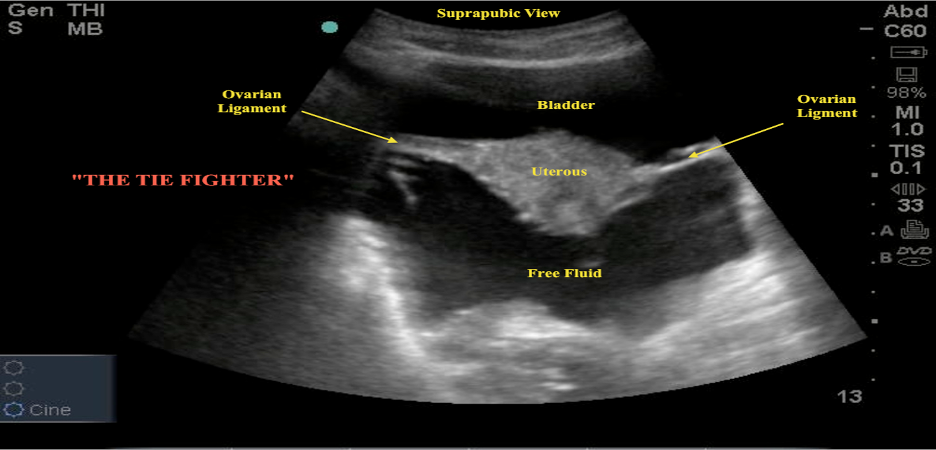

Pelvic transverse and sagittal view (Figure 19) to evaluate for free fluid in the pelvis in the dependent rectovesical space in men and the rectouterine space in women (pouch of Douglas).

Figure 19. Normal female pelvis showing relationship of uterus and bladder in a) sagittal long-axis plane and b) transverse axial plane c) large amount of free fluid in rectouterine space (Images courtesy of Matthew Lohse, MD, Baylor Scott & White-Temple)